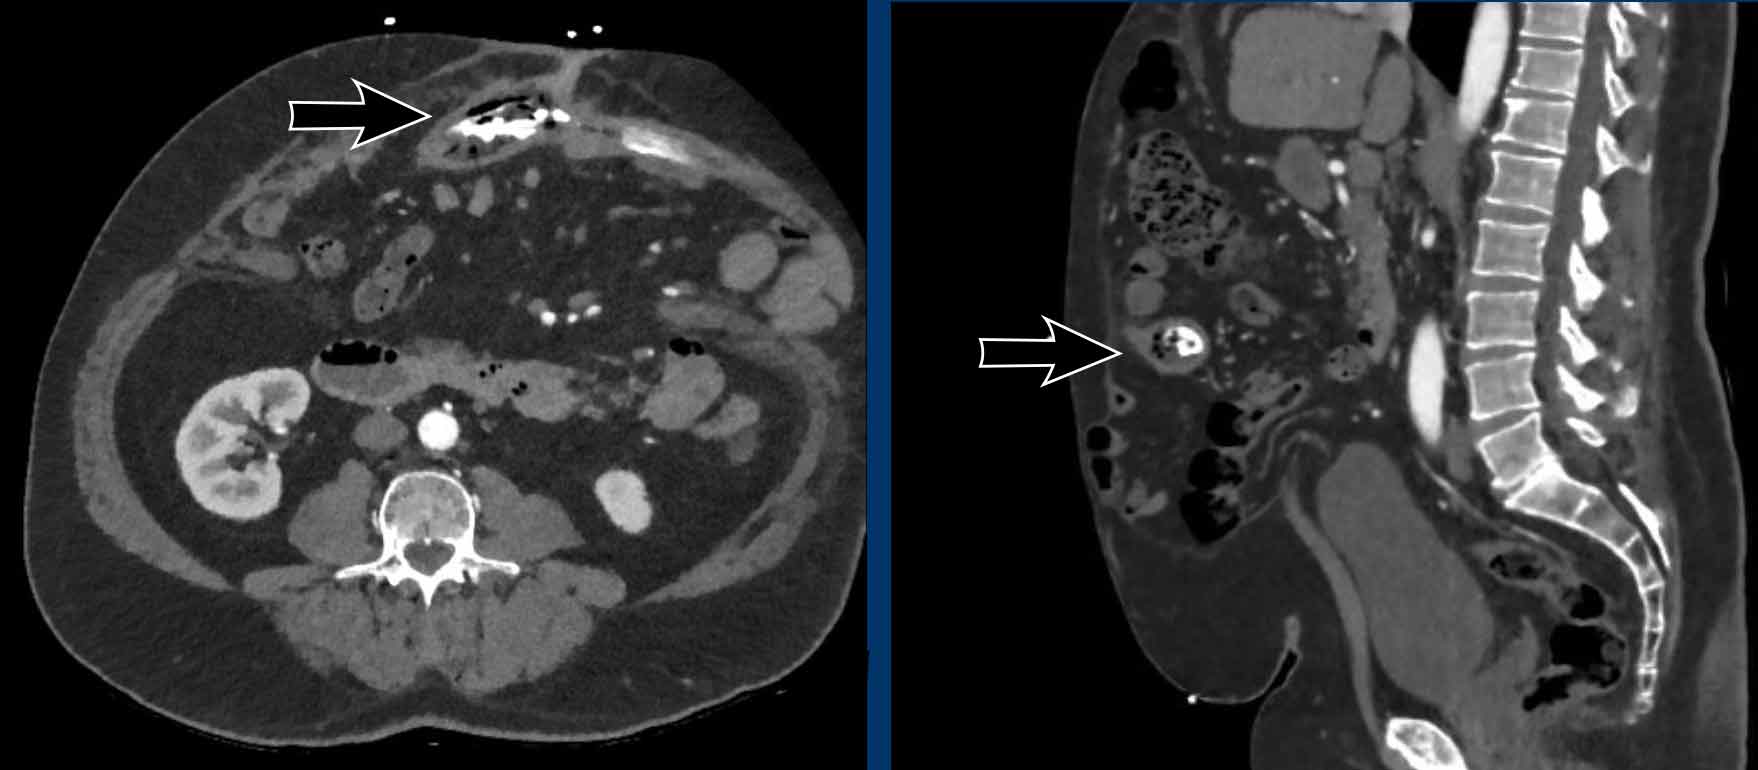

Lumbar hernia. (a) Axial computed tomography (CT) demonstrating Lumbar Hernia Radiology Assistant They are distinguished primarily based on type, location and content. We present the ct findings of seven lumbar hernias: Disc herniation is defined as a focal displacement of disc material ( < 25% of the disc circumference) beyond the limits of the. Examples of abdominal wall hernias: Abdominal hernias/herniae may be congenital or acquired and come with varying eponyms. Disc. Lumbar Hernia Radiology Assistant.